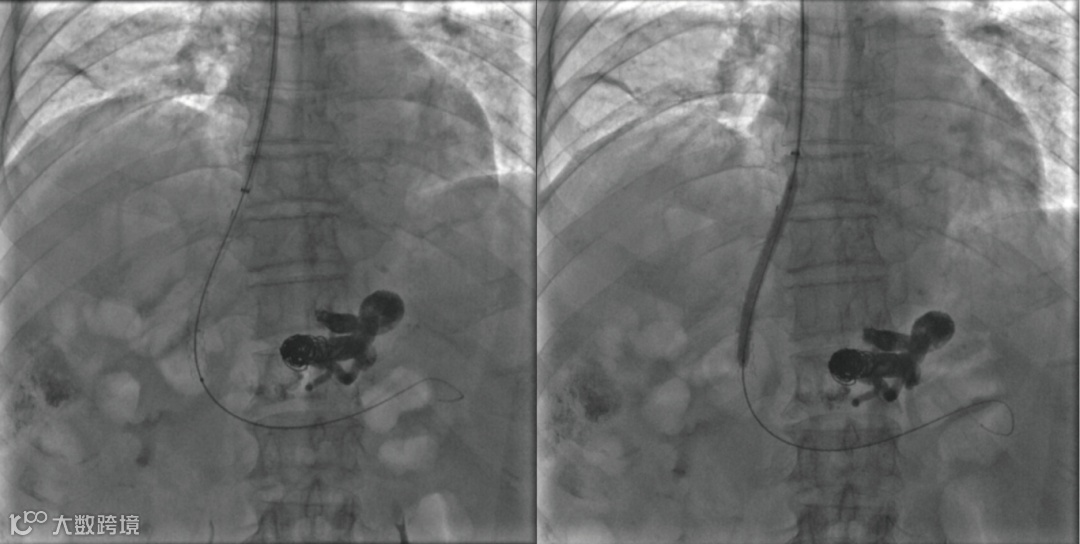

建立门体静脉分流道后行门静脉、脾静脉造影

胃冠状静脉造影

超选择插入至曲张静脉,注入弹簧圈栓塞至血流明显减缓

超选择插入至曲张静脉,注入弹簧圈栓塞,后经微导管注入聚桂醇至曲张静脉血流基本停滞

后续手术,其它器械操作:分流道成形

术后造影(即刻效果):胃底曲张静脉血管网未见显影